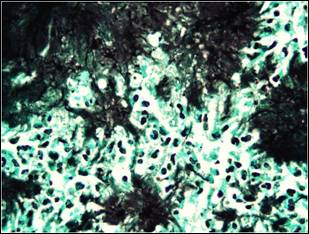

Figure 3a: A colony of

actinomyces and mixed inflammatory response at the periphery which include

histiyocytes, lymphocytes, plasmocytes, eosinophils and neutrophils. ( H&E,

original magnification x100 )

Figure 3b: Colony of filamentous

microorganisms stain black with Grocott’s methenamin silver conventional staining

method ( magnification x100 immertion ).